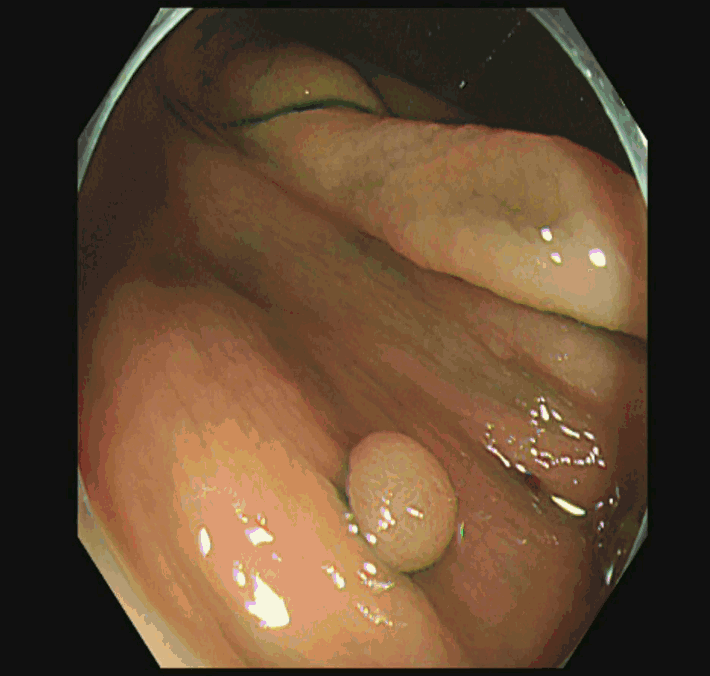

遺残・再発をゼロにするために「十分に周囲を大きく切除する必要」があります(「Extended Cold法」と呼ばれます)

Extended Cold法法で切除された検体は「目玉焼き」のようになります。「黄身」が病変で、「白み」が周囲の正常組織(余白、マージン)です。